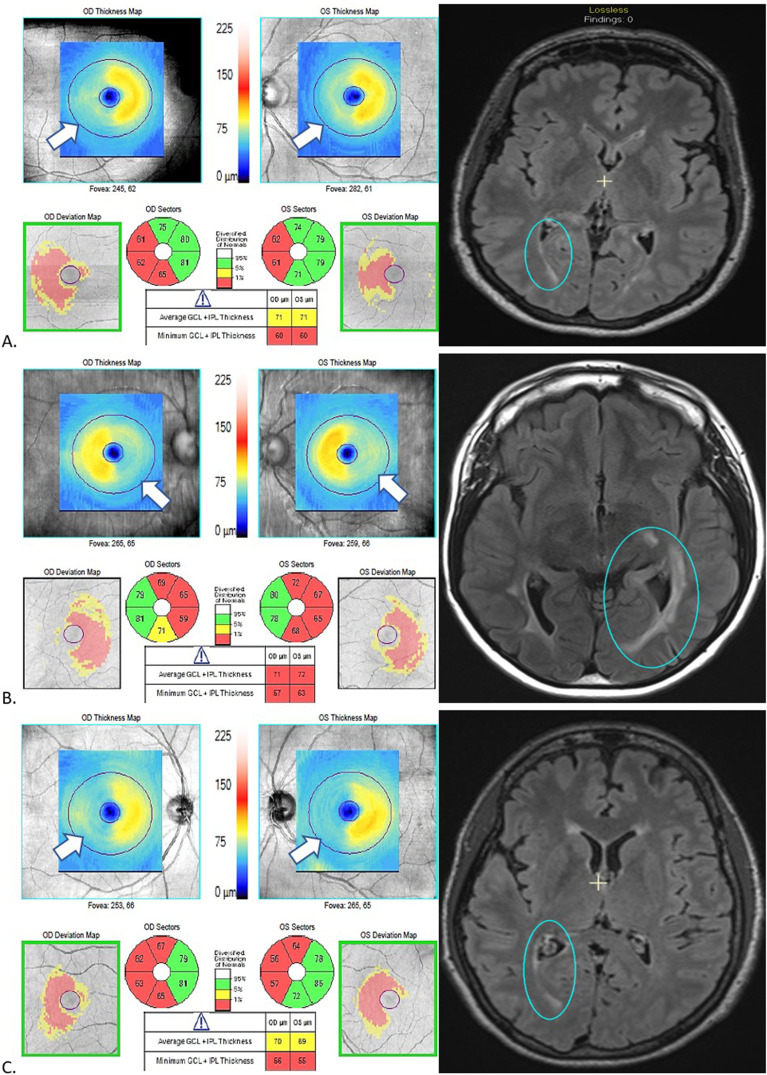

多发性硬化症(MS)神经退行性变的一种假定机制是跨突触变性(TSD),即神经元损伤导致突触相连的神经元变性。多发性硬化症通常涉及视觉系统,而视觉系统结构明确,因此是研究 TSD 的理想模型。TSD可能发生在前向方向(视神经病变导致后视通路变性,包括视神经放射和枕灰质)和/或后向方向(后视通路病变导致视网膜变性)。在本综述中,我们讨论了支持多发性硬化症患者视觉系统存在逆行和顺行 TSD 的证据。

A putative mechanism of neurodegeneration in multiple sclerosis (MS) is trans-synaptic degeneration (TSD), whereby injury to a neuron leads to degeneration of synaptically connected neurons. The visual system is commonly involved in MS and provides an ideal model to study TSD given its well-defined structure. TSD may occur in an anterograde direction (optic neuropathy causing degeneration in the posterior visual pathway including the optic radiations and occipital gray matter) and/or retrograde direction (posterior visual pathway lesions causing retinal degeneration). In the current review, we discuss evidence supporting the presence of anterograde and retrograde TSD in the visual system in MS.